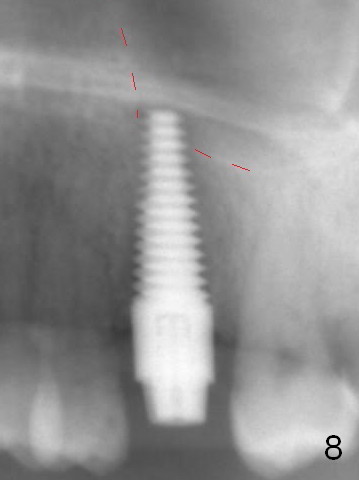

The septum perforates into the distobuccal socket when 4.3 mm drill is being used. The sinus floor bone (Fig.5 *, Fig.6-8 red dashed line) has to be used for primary stability. Finally a 6x20 mm tap achieves stability apparently by engaging to the mesial and distal walls of the socket (Fig.6). The insertion torque of a 6x20 mm tissue-level implant is > 60 Ncm (Fig.7) with allograft packed into the remaining socket (*).